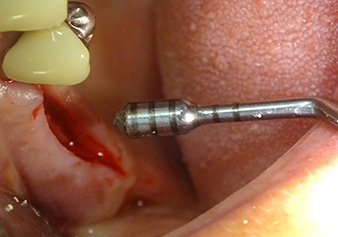

Lo strumento I2A (diametro 2,0 mm) è stato quindi impiegato per perforare il pavimento sinusale in modo graduale e su superfici molto ridotte. Tale metodo piezochirurgico previene il danneggiamento della membrana di Schneider. Durante l'utilizzo di Z25P, la membrana risultava già essere leggermente sollevata dal fluido di raffreddamento fornito attraverso la punta dello strumento (Fig. 3). La quantità di fluido di raffreddamento presente era solo del 50% per evitare che la sede dell'impianto registrasse un'elevata pressione.